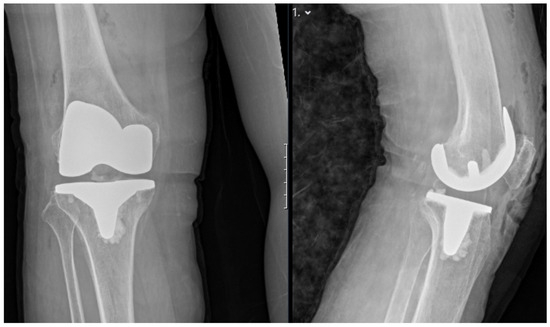

Figure 5.

Postoperative standing anteroposterior (left) and lateral (right) X-rays of the right knee demonstrating appropriate alignment and positioning of the total knee prosthesis.